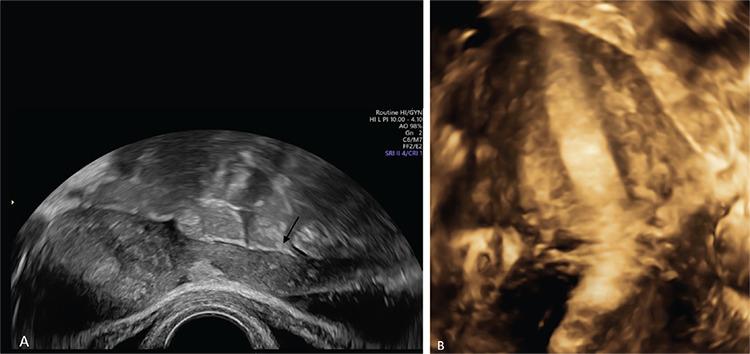

Endometriosis is one of the most common benign diseases in women of reproductive age. Nearly all gynecological offices and clinics will contain patients with endometriosis; the frequency and severity of the disease will vary from one setting to another. Adjoining specialties, such as internal medicine, general medicine, surgery, urology, orthopedics, neurology and psychosomatic medicine, will be challenged directly or indirectly by various forms of endometriosis and its sequelae. The disease is characterized by pelvic pain, dysmenorrhea, dyspareunia and sterility. Even now, several years may elapse between the onset of the disease and its diagnosis. The diagnosis of endometriosis is complicated by the diversity of the symptoms. A precise documentation of the patient’s medical history and thorough diagnostic procedures are essential to establish a robust diagnosis. This article will discuss the perioperative considerations, diagnosis and treatment of endometriosis.